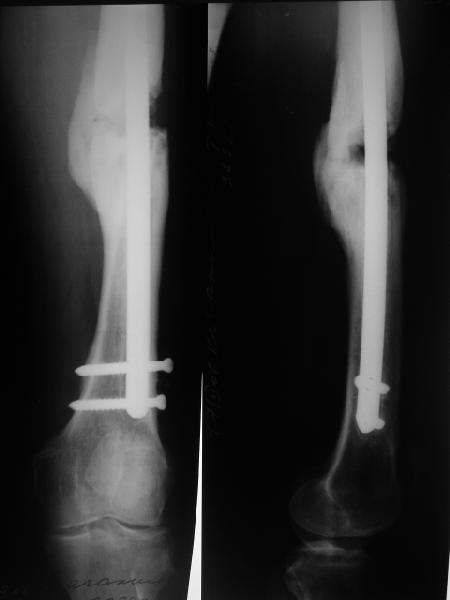

В приложении снимки бедра - с такой картинкой пациентка ходит, не хромает, работает инженером 3,5 года после операции с первых дней, хотя еще и инсулинозависимый диабет.

У нас есть все же сомнения, насколько он "тугой". Наличие хоть и нестабильной но все же фиксации пластиной, маскирующей степень подвижности; сочетание на рентгенограммах зон гиперостоза с зонами лизиса не дает четкой уверенности ни в том, что это тугой ложный сустав в классическом понимании, ни что это истинно атрофическая ситуация. А чем сейчас можно быть уверенным? Вот потому и одолевают сомнения.

> В приложении снимки бедра

Наш пациент имеет рост 2 м и вес 120 кг, при этом он не выглядит полным. Так что не очень хочется надеяться только на гвоздь, хотелось бы и репаративные процессы обеспечить.